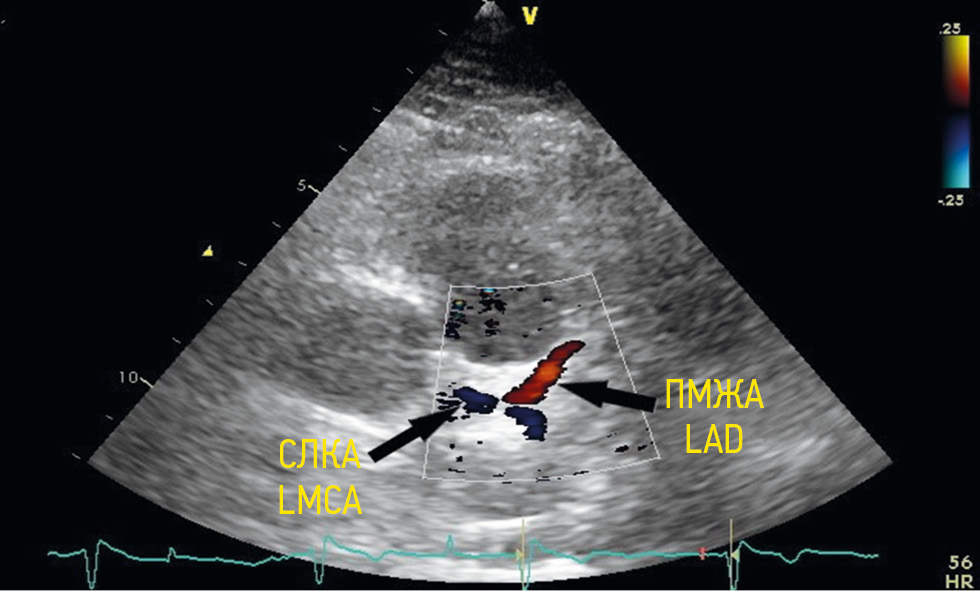

To visualize the left coronary artery trunk, a normal antegrade blood flow in red or blue (red was detected by flow directed to the transducer, and blue was from the transducer) was determined using color Doppler imaging in the area of the left coronary sinus depending on anatomical features of the chest, transducer position, and left coronary artery origin (Figure 1).

Fig. 1. Vizualization of the left main coronary artery from a modified left parasternal position along the long axis. LMCA — left main coronary artery; LAD — left anterior descending artery / Рис. 1. Визуализация ствола левой коронарной артерии из модифицированной левой парастернальной позиции по длинной оси. СЛКА — ствол левой коронарной артерии; ПМЖА — передняя межжелудочковая артерия